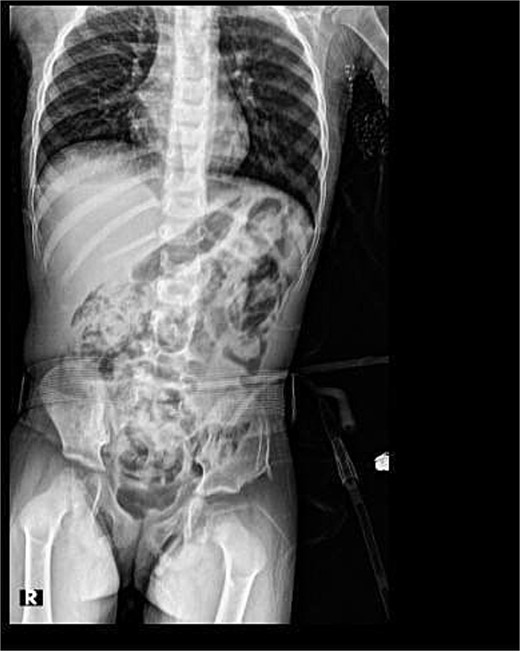

Her post-operative course was unremarkable. An evaluatory X-ray 3 days post-op revealed good outcomes (Fig. 2).